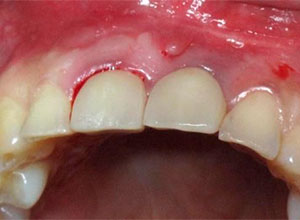

Sindesmotomía del tejido

Extracción, limpieza y curetaje del alveolo

Poste direccional del implante

Material osteogénico en masa

Sutura y reconstrucción del tejido blando papilar

Dejamos que el implante se oseointegre para terminar con la rehabilitación protésica.